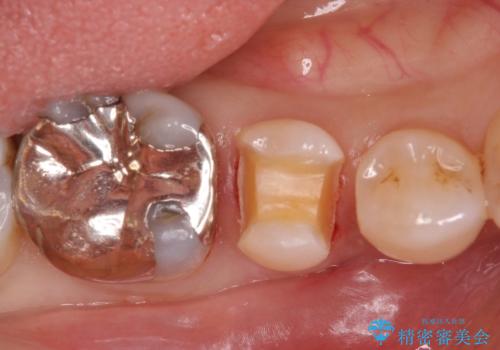

銀歯を外し、拡大鏡下で虫歯を全て取り除き、白い詰め物(e-maxインレー)にて治療することになりました。

まずは一つ治療したいとの事だったので手前の小臼歯から行いました。